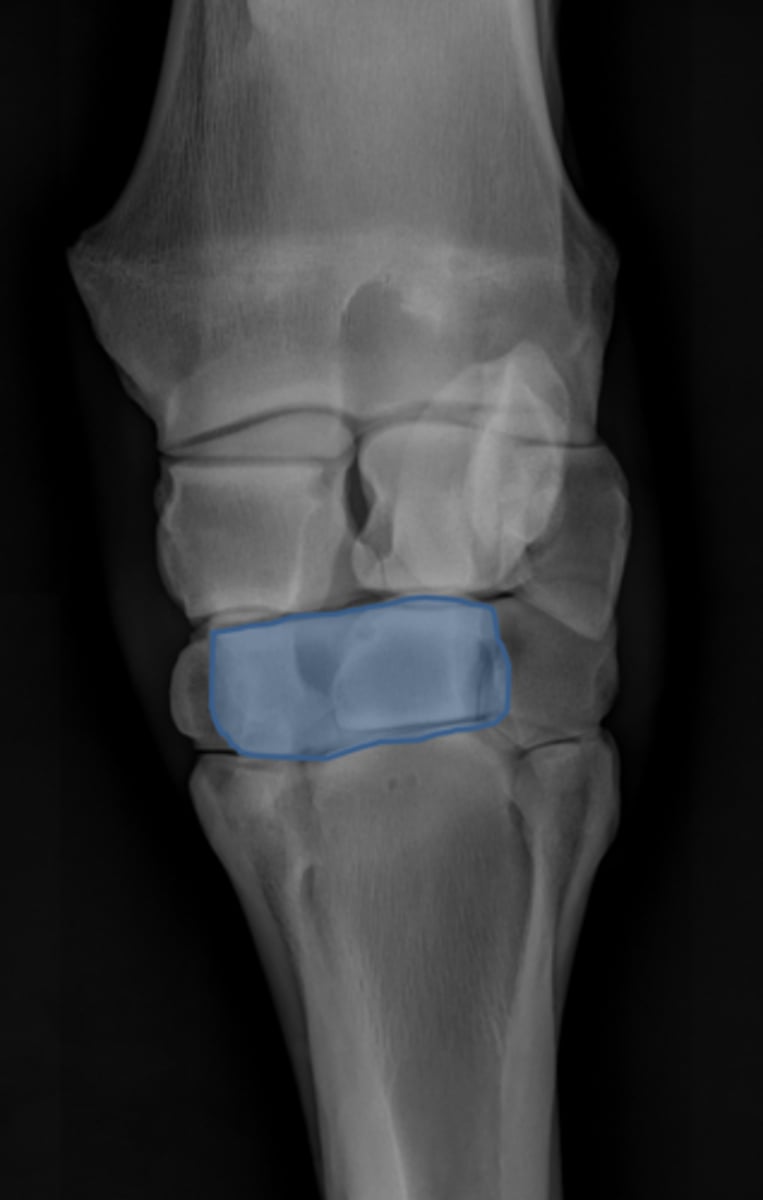

Carpus, lateral

ID joint and view

Antebrachiocarpal joint

Middle carpal joint

Carpometacarpal joint

Radial carpal bone

Intermediate carpal bone

Ulnar carpal bone

Third carpal bone

Second carpal bone

Fourth carpal bone

Accessory carpal bone

Second metacarpal (medial splint)

Fourth metacarpal (lateral splint)

Cannon bone

Up, down

For a flexed lateral view of the carpus the intermediate carpal bone moves __________ and the radial carpal bone moves _________

Down, up

For a flexed lateral view of the carpus the third carpal bone moves __________ and the fourth carpal bone moves _________

Intermediate carpal bone

Radial carpal bone

Third carpal bone

Fourth carpal bone